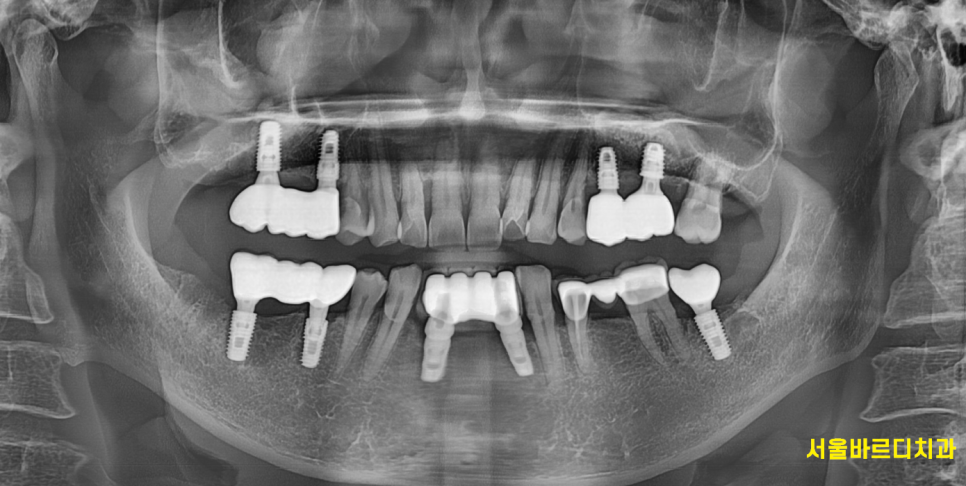

250313 성공적인 임플란트 수술을 위해서!

<오늘 글 결론>

임플란트 시술 성공률은 평균적으로 90~98%입니다.

하지만 다양한 요소가 성공률에 영향을 미칠 수 있습니다.

때문에 실패를 유발할만한 원인이 무엇이 있을까

의료진과의 상의는 필수랍니다!!